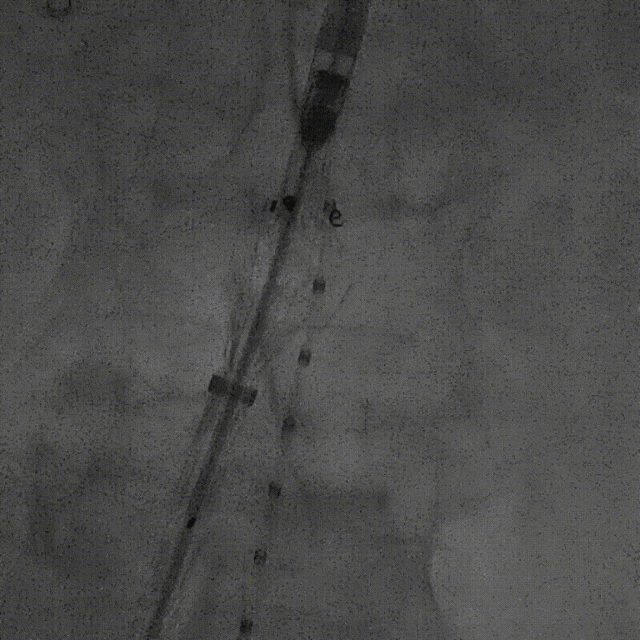

该技术主要适用于采用旋转式释放机制的支架。其核心操作步骤为:在主体支架释放出前2-3节后,轻微松开支架,然后反复反向旋转并上推输送鞘。 这一动作能促使已释放的近端支架段在瘤颈处产生可控的“堆叠”效应,从而更好地顺应瘤颈的弯曲形态,尤其是在大弯侧实现更紧密的贴壁,有效拓展了功能性密封区。

案例一(巨大成角瘤颈):患者瘤颈虽长但呈90度成角。在完成髂动脉重建后,采用Reverse技术释放主体支架。术中造影显示,支架完美贴合扭曲的血管大弯侧,术后一月复查CTA,原有的少量内漏已完全消失。

案例二(短瘤颈+梯形瘤颈):患者近端瘤颈长度不足1cm,且伴有大量附壁血栓。选用适当oversize的支架,结合Reverse技术释放,支架主体自动“寻找”并适应最佳的贴附区域,最终造影显示无明确内漏。

截至目前,采用Reverse技术处理不良瘤颈的初步经验(21例)显示,术中发生明显I型内漏仅3例,其中2例经弹簧圈栓塞处理,1例在随访中自行消失。这表明Reverse技术在处理不良瘤颈时,是一种安全、有效且能显著减少内漏发生的手段。